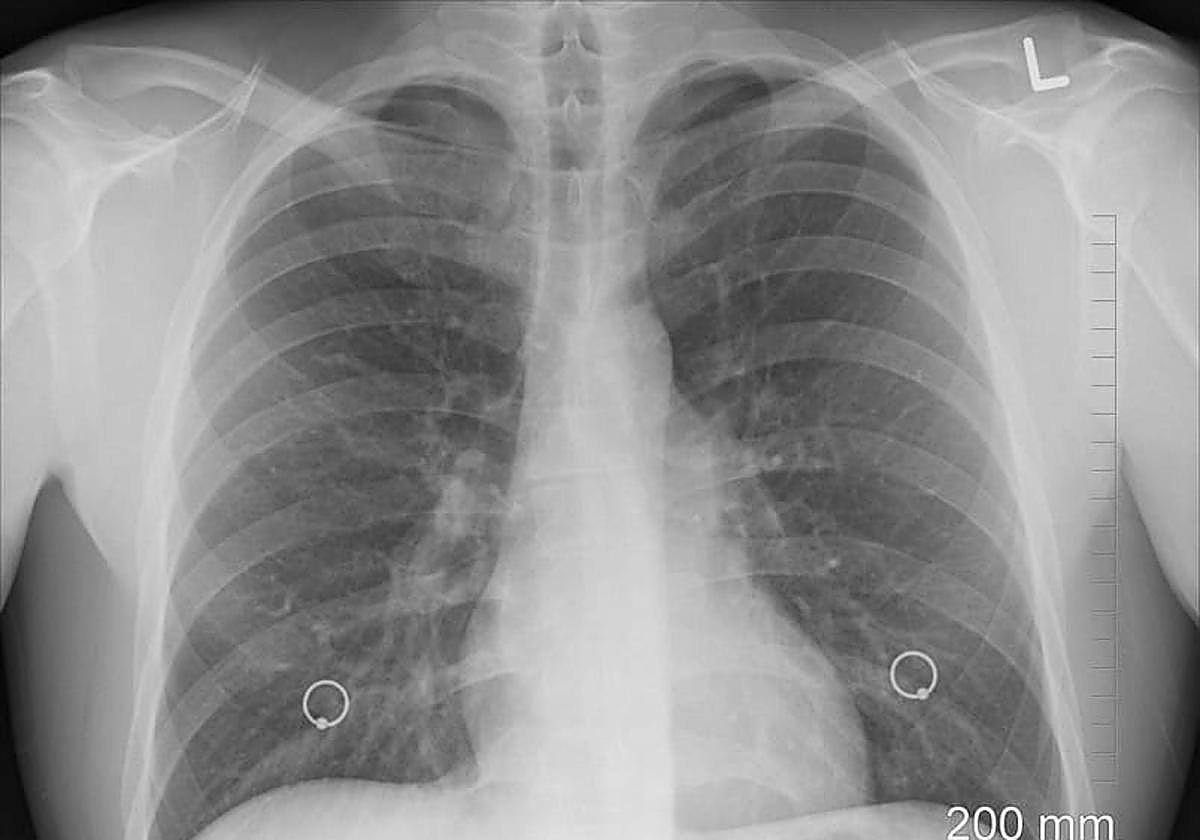

Detección y diagnóstico

Para el diagnóstico, además de las técnicas de imagen, es necesario realizar una biopsia, que puede hacerse bien por vía endoscópica o por parte de cirugía, como aporta el Dr. Cózar, cirujano torácico de Viamed.